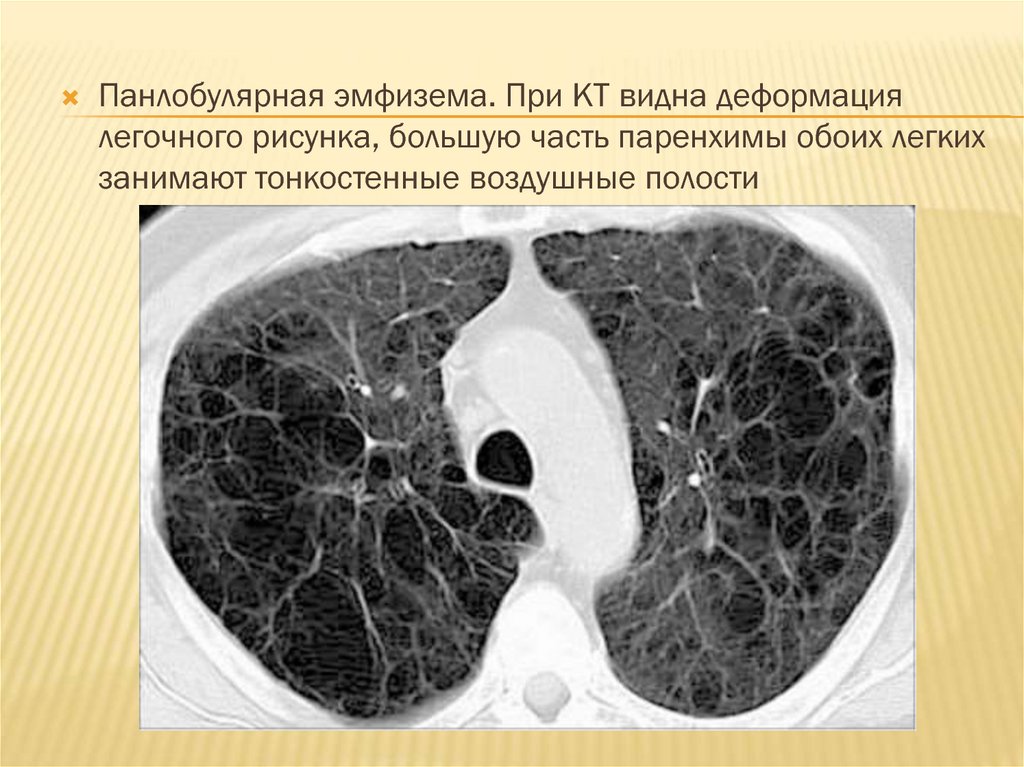

Множественные БУЛЛЫ В ЛЕГКИХ на КТ РАСШИФРОВКЕ и подозрение на синдром Маклеода

Эмфизема легких.

ХОБЛ - эмфизема легких на КТ заключении грудной клетки (КТ второе мнение)